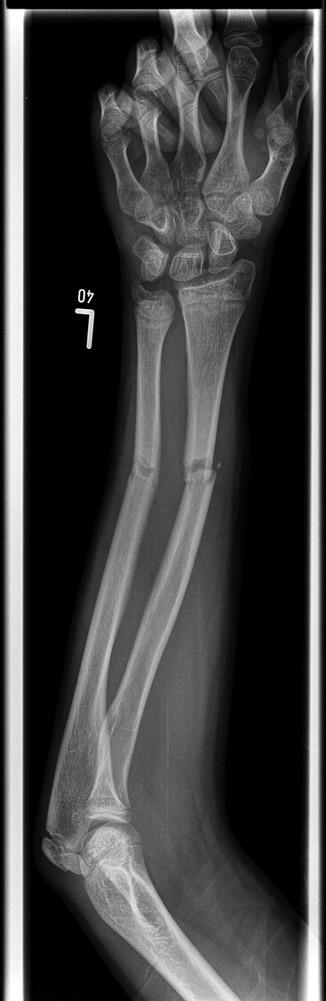

A 12-year-old male patient sustained a closed midshaft both-bone forearm fracture of their non-dominant arm from a fall on a trampoline (Figs 1 and 2). Anatomical reduction was achieved with a manipulation under anaesthesia (MUA), but it was noticed that there was a mechanical block to extension of the ring finger. The radius and ulna were therefore approached through separate incisions and it was discovered that the FDP was entrapped at the ulna fracture at the level of the musculotendinous junction. Following release the fingers regained a full range of motion and the patient went on to heal without further complication (Figs 3 and 4).

Pre-operative lateral radiograph showing dorsally angulated both-bone forearm greenstick fracture.